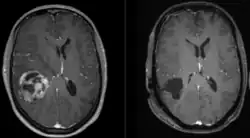

Glioblastoma pre (left) and post (right) resection.

Surgery is the first stage of treatment of glioblastoma. An average GBM tumor contains 1011 cells, which is on average reduced to 109 cells after surgery (a reduction of 99%). Benefits of surgery include resection for a pathological diagnosis, alleviation of symptoms related to mass effect, and potentially removing disease before secondary resistance to radiotherapy and chemotherapy occurs.[67]

The greater the extent of tumor removal, the better. In retrospective analyses, removal of 98% or more of the tumor has been associated with a significantly longer healthier time than if less than 98% of the tumor is removed.[68] The chances of near-complete initial removal of the tumor may be increased if the surgery is guided by a fluorescent dye known as 5-aminolevulinic acid.[69][70] GBM cells are widely infiltrative through the brain at diagnosis, and despite a "total resection" of all obvious tumor, most people with GBM later develop recurrent tumors either near the original site or at more distant locations within the brain. Other modalities, typically radiation and chemotherapy, are used after surgery in an effort to suppress and slow recurrent disease through damaging the DNA of rapidly proliferative GBM cells.[71]